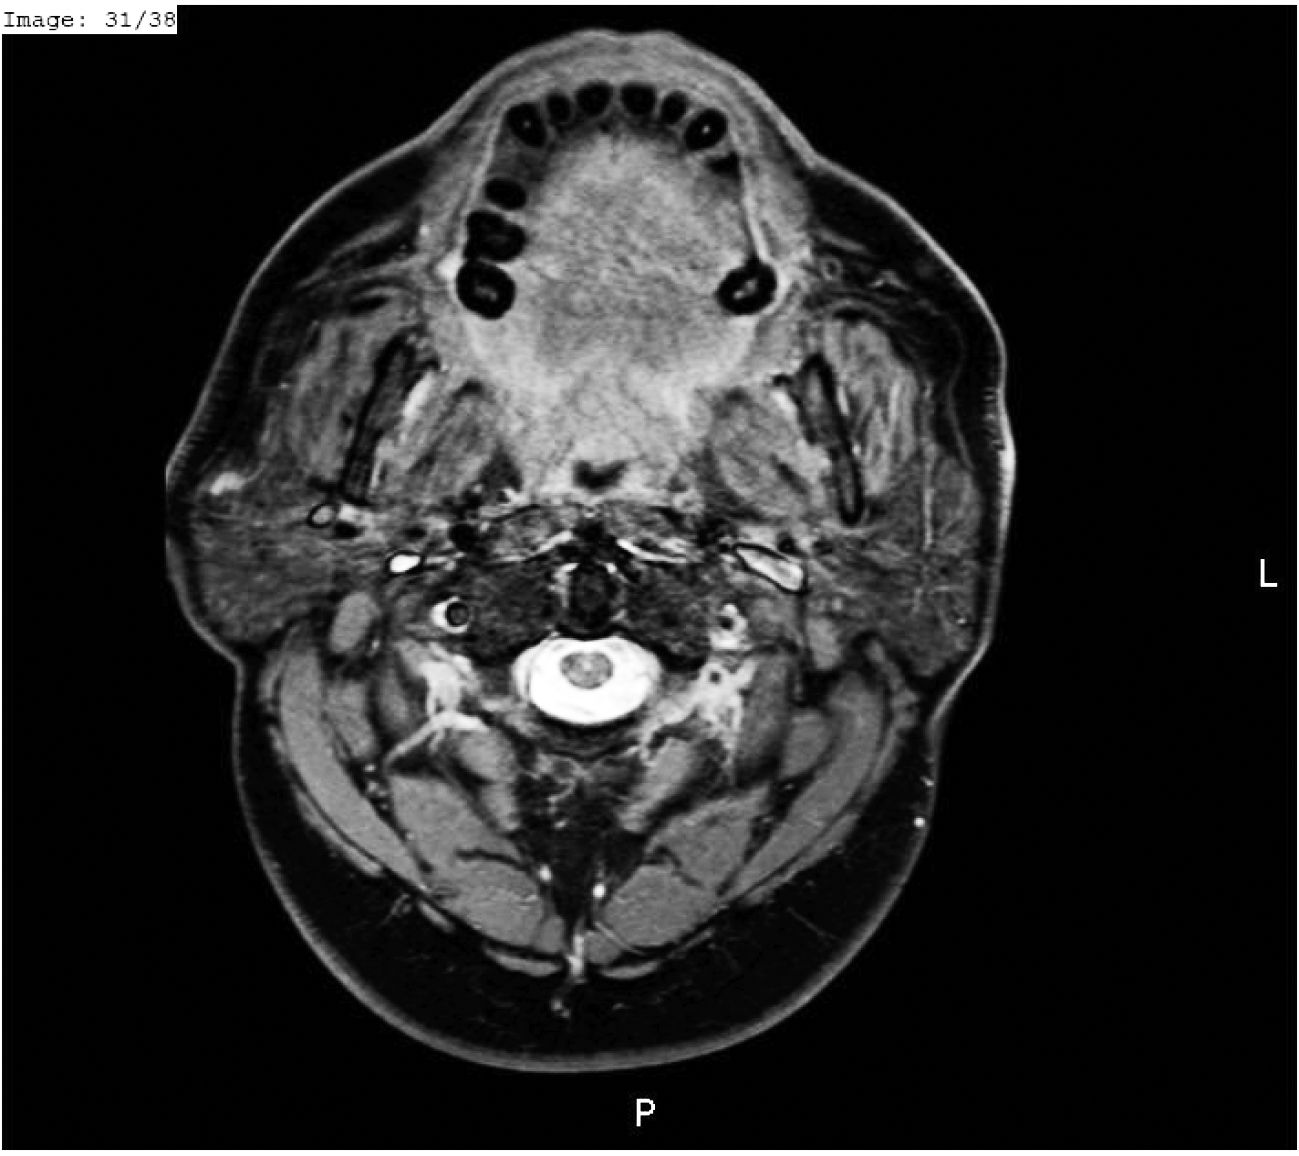

Durante la primera semana del mes de noviembre de 2018 le efectúan una TC de encéfalo y tórax con contraste EV (iopamidol); 36 horas más tarde, el paciente concurre a la consulta relatando dolor en región submandibular y cuello. Minutos después de finalizar el estudio comienza a percibir molestias mal caracterizadas en dichas zonas, notando edema progresivo y dolor. Al examen se constata tumefacción de región submandibular, retromandibular, cuello y piso de la boca, Lóbulos de las orejas desplazados hacia afuera, simétricos. Se palpan las seis glándulas salivales principales agrandadas de manera simétrica, dolorosas, sin rodetes eritematosos en las desembocaduras de los conductos salivales. Las glándulas submaxilares se palpan de forma ovoide y miden aproximadamente 6 cm de largo, se encuentran tensas y despiertan intenso dolor (Imagenes 1 y 2). El resto de las glándulas principales muestran similares características palpatorias. Niega fiebre y sus equivalentes.

Se solicita ecografía que demuestra glándulas salivales agrandadas sin alteraciones en el parénquima a destacar. Relata que unas pocas horas después del estudio contrastado, al comer, nota incremento del dolor y deformación en el cuello. Se efectúa tratamiento de hemodiálisis habitual y, durante el mismo, se administra hidrocortisona 500 mg por vía EV, AINE´s por vía oral. Una hora más tarde, refiere atenuación del dolor y se observa disminución generalizada del edema en forma simétrica. Se le indican AINE´s y antibacterianos. En la tercera semana muestra resolución parcial con tumefacción de las glándulas parótidas y submaxilar izquierda.(Imagines 3, 4 y 5)